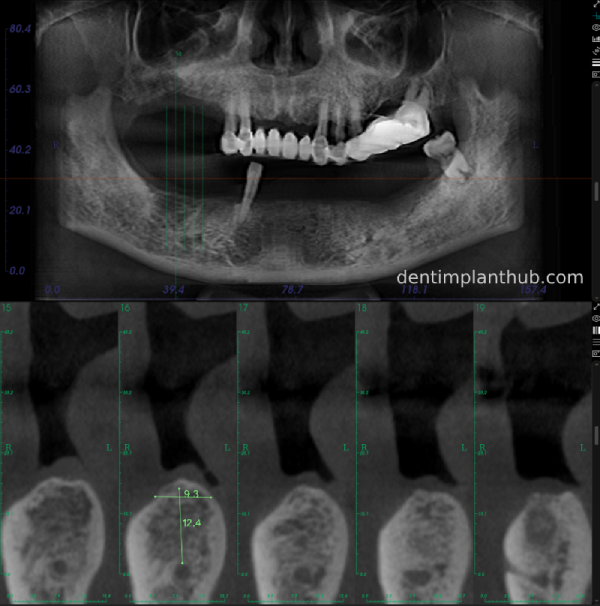

A review of the CBCT on 6/10/23 was more promising and a surgical plan was subsequently drawn up.

46

44

42

32

34

36

General schematic of the surgical programme

Detailed list of implant types and composite abutments to be prepared.

46 tooth position, implant model number 4810, RC series straight composite abutment;

44 tooth position, implant model number 4110, RC series straight composite abutment;

42 tooth position, implant model number 4110, RC series straight composite abutment; alternate implant model number 3310, alternate NC series straight composite abutment;

32 tooth position, implant model number 4110, RC series straight composite abutment; alternate implant model number 3310,. Alternate NC Series Straight Composite Abutment;

34 Dental Position, Implant Model No. 4110, RC Series Straight Composite Abutment;

36 Dental Position, Implant Model No. 4808, RC Series Straight Composite Abutment;